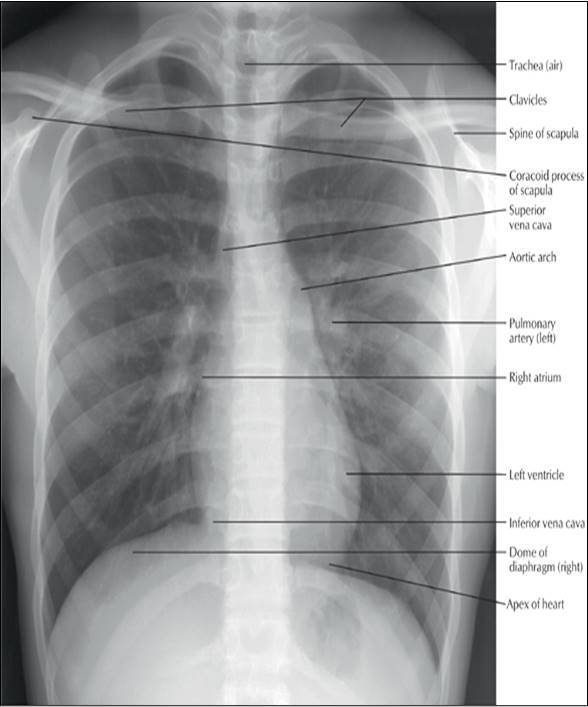

Identify the tagged structures!